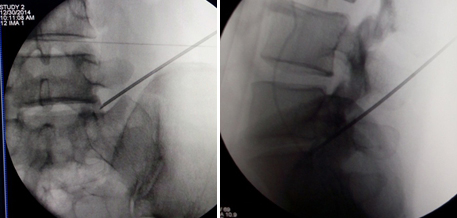

(图)体表定位

(图)穿刺针定位

(图)置入扩张管